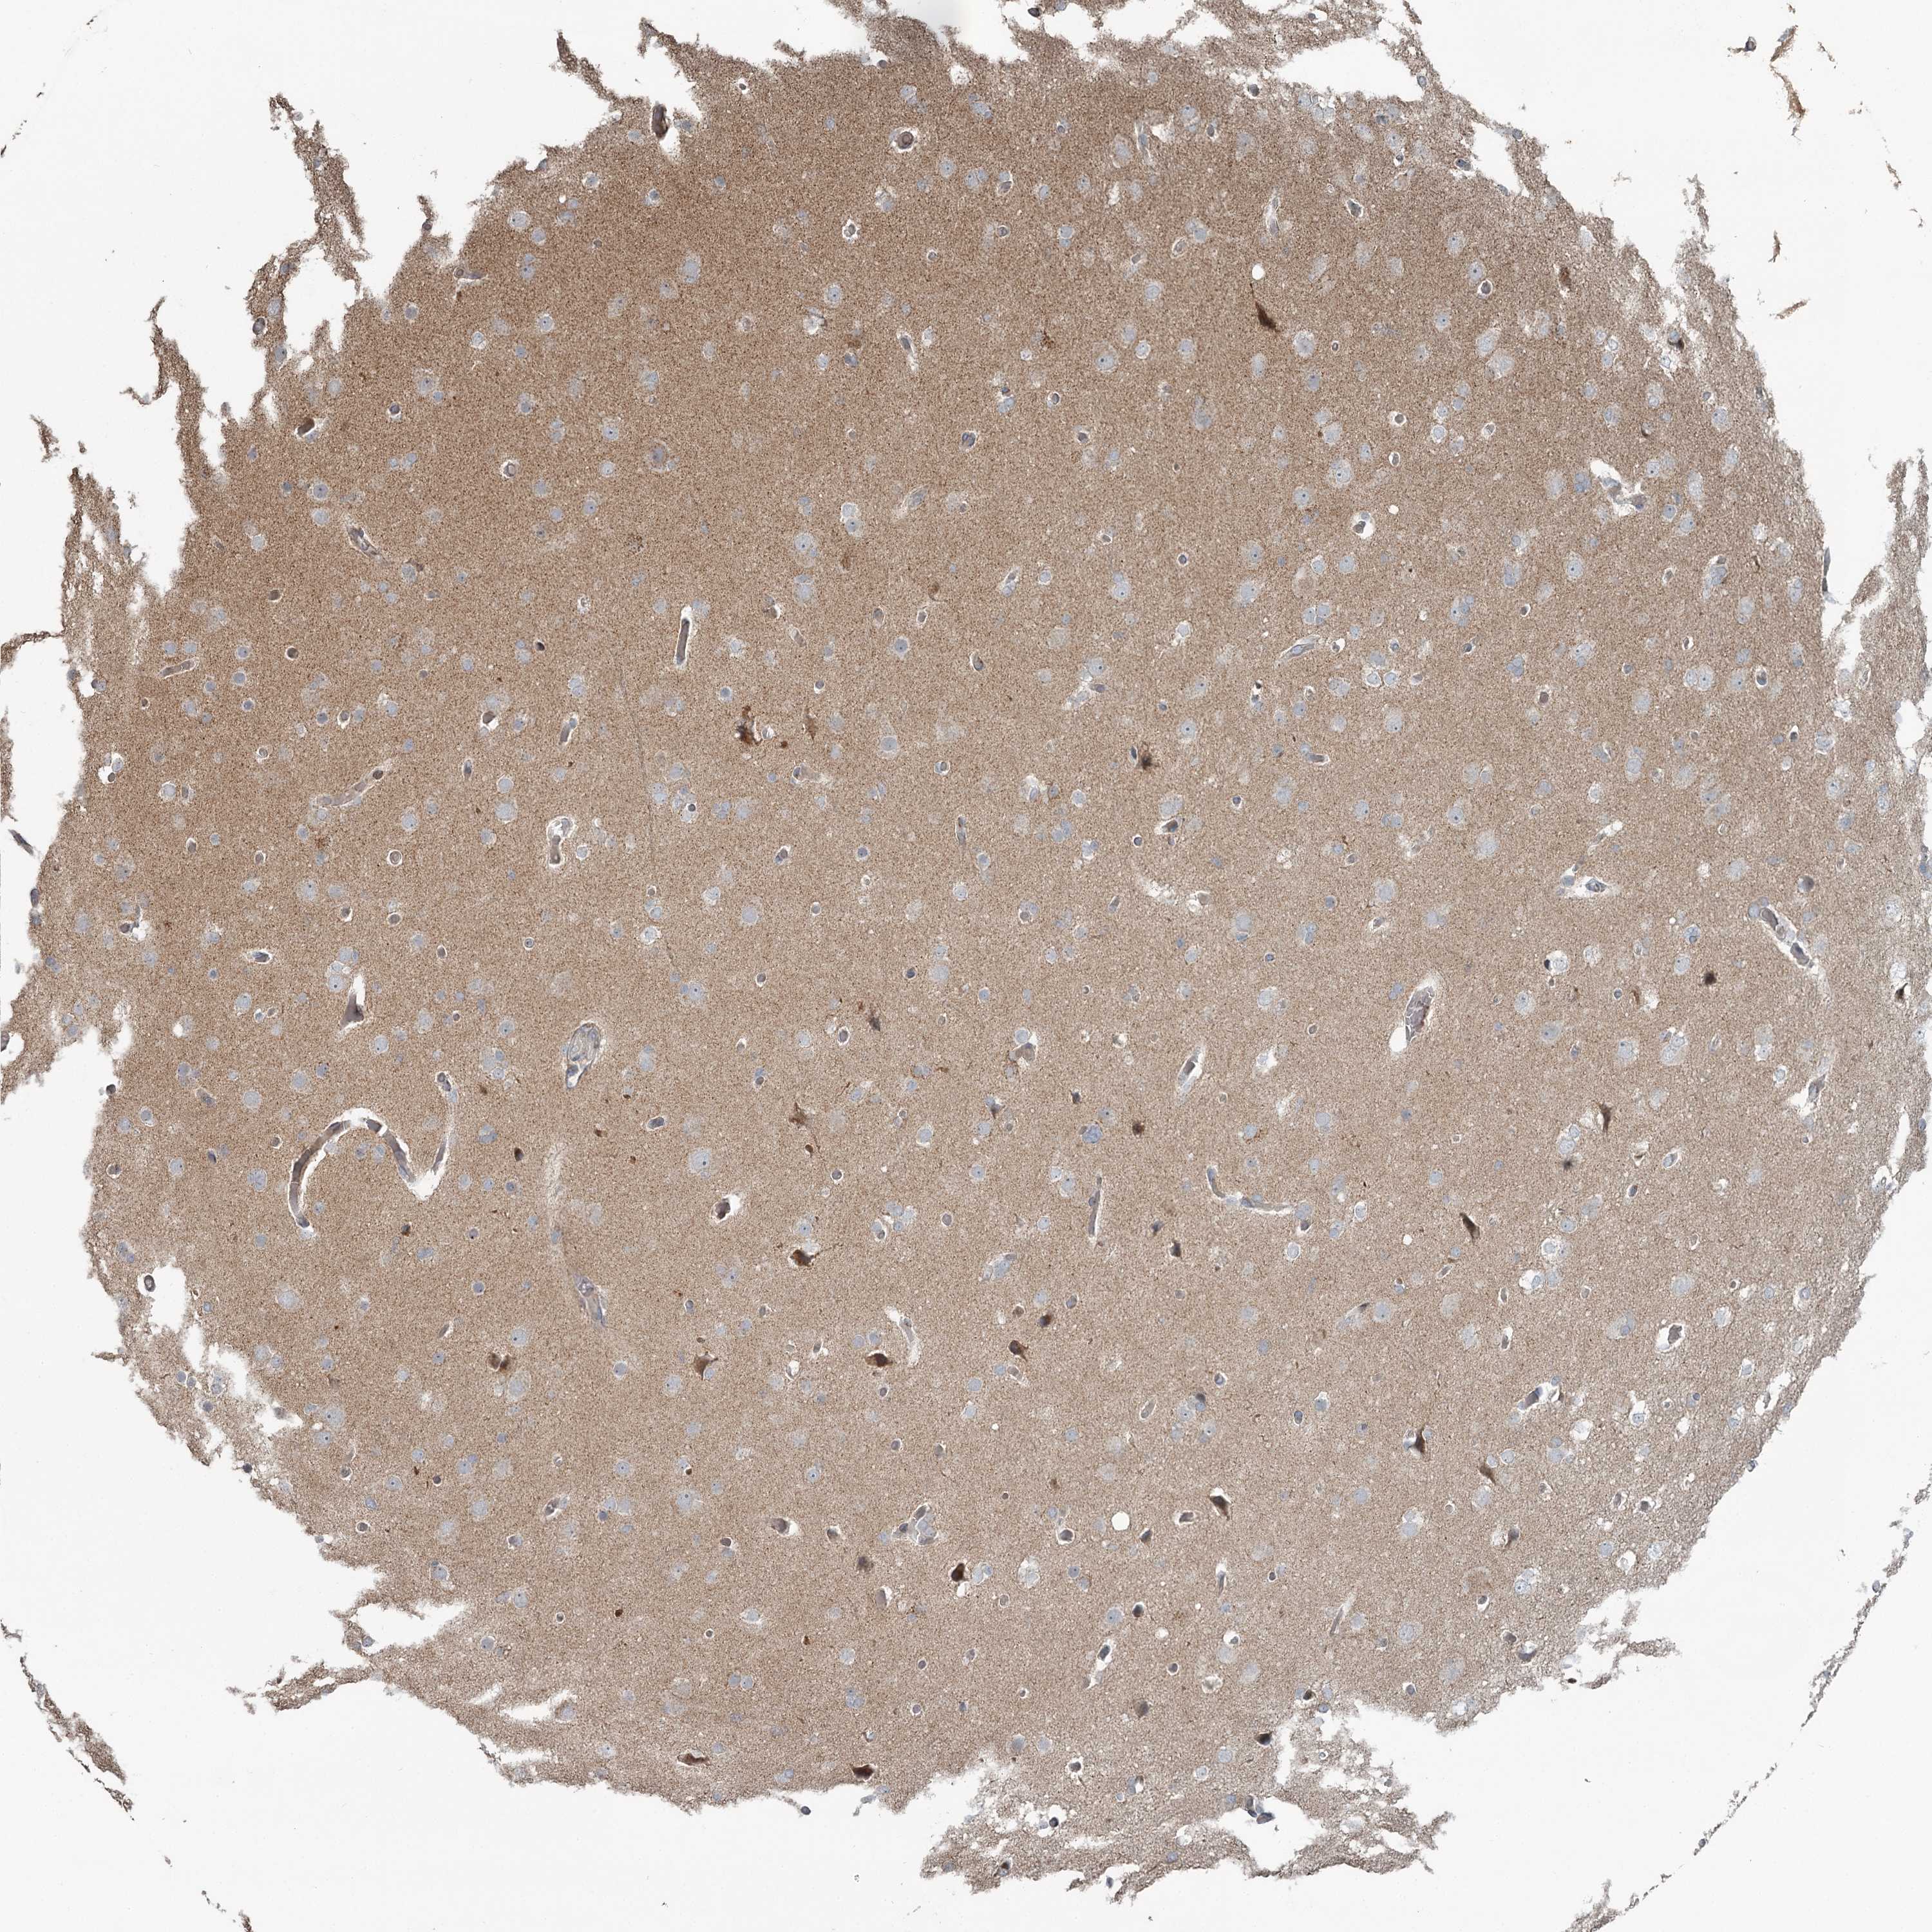

GLIOMA - Protein expressioni

A mouse-over function shows sample information and annotation data. Click on an image to view it in a full screen mode. Samples can be filtered based on level of antibody staining by selecting one or several of the following categories: high, medium, low and not detected. The assay and annotation is described here.

Note that samples used for immunohistochemistry by the Human Protein Atlas do not correspond to samples in the TCGA dataset.

Antibody stainingi

Antibody staining in the annotated cell types in the current human tissue is reported as not detected, low, medium, or high, based on conventional immunohistochemistry profiling in selected tissues. This score is based on the combination of the staining intensity and fraction of stained cells.

Each image is clickable and will lead to virtual microscopy that enables deeper exploration of all samples and also displays staining intensity scores, fraction scores and subcellular localization as well as patient and tissue information for each sample.

Antibody HPA038163

Antibody HPA038164

Staining

High

Medium

Low

Not detected

Intensity

Strong

Moderate

Weak

Negative

Quantity

>75%

75%-25%

<25%

None

Location

Nuclear

Cytoplasmic/membranous

Cytoplasmic/membranous,nuclear

Glioma, malignant, High grade

Glioma, malignant, Low grade

Glioblastoma, NOS